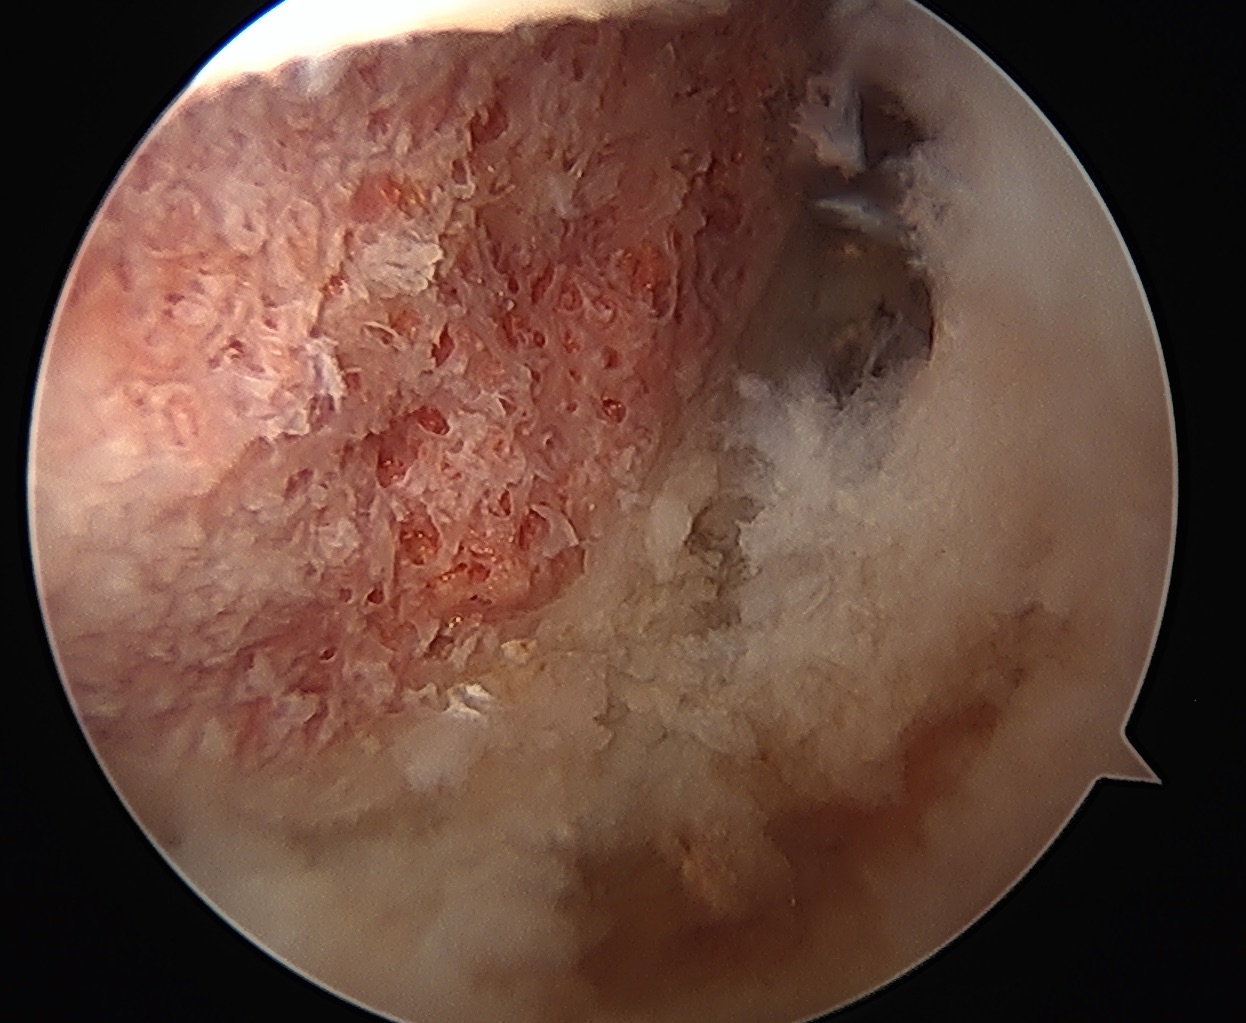

During this keyhole procedure, anchors with sutures are used to repair the labral tear. Extra bone is taken away from the acetabulum and the femoral head / neck area as needed. Usually the hip capsule is opened to access the hip joint fully, and this is carefully closed at the end of surgery.